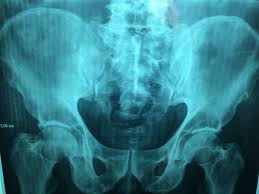

고관절 통증이 나타나는 위치

고관절 통증은 엉덩이 깊숙한 부위에서만 느껴진다고 생각하기 쉽지만, 실제로는 다양한 위치로 퍼져 나타날 수 있습니다.